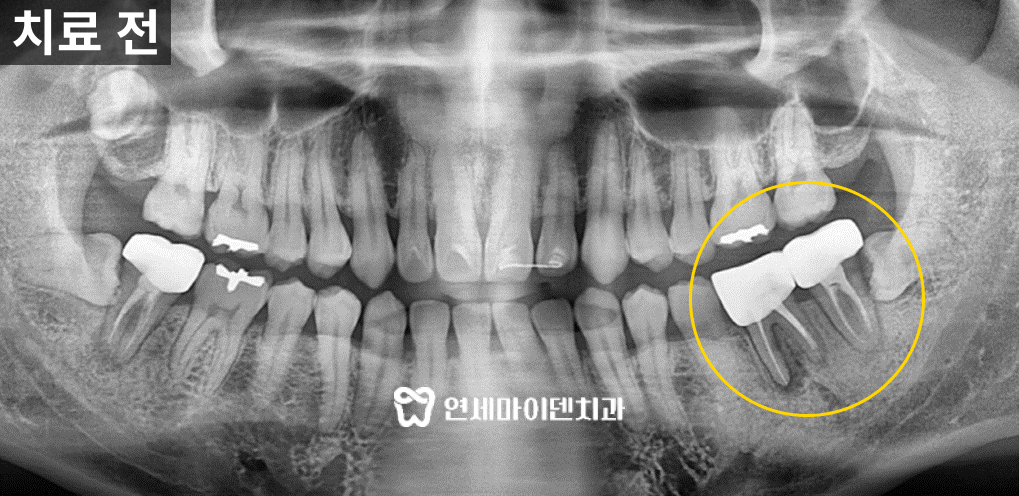

이 환자분은 아래쪽 어금니 2개에 문제가 있었습니다.

염증이 크고 다른 치과에서 발치 권유를 받았지만

최대한 치아를 살리고 싶으셔서 저희 병원을 찾아오셨습니다.엑스레이 상에서 넓은 부위의 염증을 확인했지만

저희 병원은 ‘내치아지키기’ 프로젝트로 자연치아 보존을 최우선으로 하기 때문에

환자분의 니즈대로 우선 신경치료부터 시도해보기로 했습니다.

신경치료를 하기 전 어금니에 씌워져 있던 크라운을 제거하고

미세현미경으로 내부를 확인하였습니다.이 과정에서 엑스레이로 확인되지 않았던

치아의 금, 즉 크랙라인이 확인되었습니다.금이 간 치아는 살릴 수 없나요?

이 환자분도 미세현미경 상으로 명백한 크랙라인이 확인됐기 때문에

지체없이 발치한 후 임플란트를 진행하기로 했습니다.당일 수술이 결정되었지만, 3D 네비게이션 정밀 진단을 통해